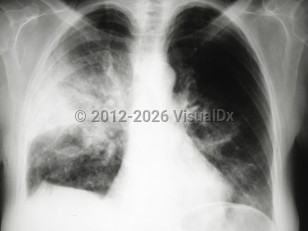

Chest pain, Dyspnea, 50-59 year old Female

Pneumothorax

Spontaneous pneumothoraxSpontaneous pneumothorax